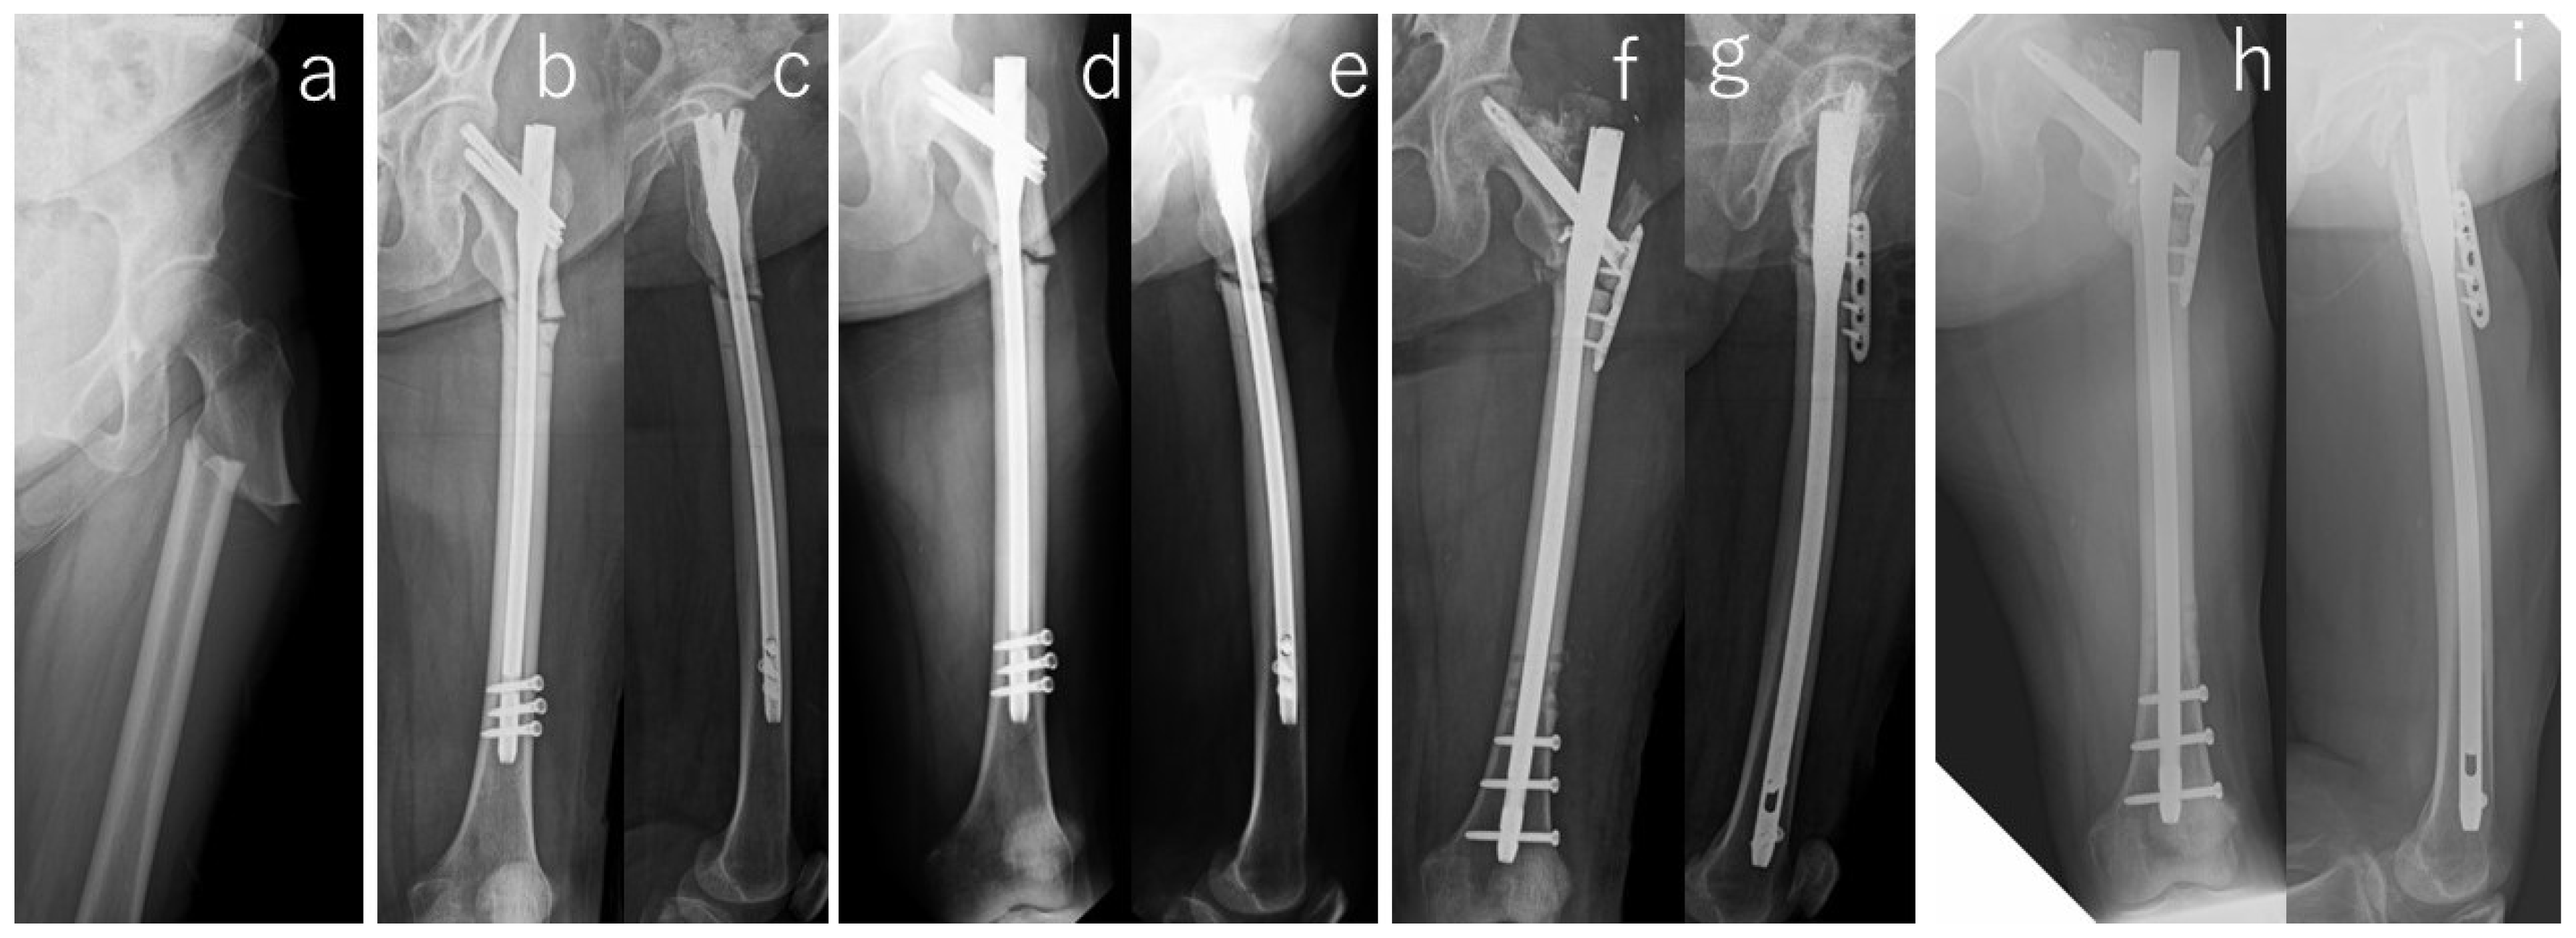

| Implant | Operative Procedure | Adjuvant Therapy | Malalignment | Cortical Discontinuity (-/Direction) | Fracture Gap | Correction Loss | Duration of Bone Union/Nonunion | ||||||

|---|---|---|---|---|---|---|---|---|---|---|---|---|---|

| Open Reduction | Bone Graft | Drilling | LIPUS # | Teriparatide | AP View | Lateral View | AP View | Lateral View | AP View | Lateral View | |||

| Antegrade intramedullary nail | - | - | - | - | - | - | - | - | Posterior | + | - | - | 6 months |

| Antegrade intramedullary nail | - | - | - | - | - | - | - | - | Posterior | + | - | - | 10 months |

| Cephalomedullary long nail | - | - | - | - | - | Varus | - | - | Posterior | - | - | - | Non-union (atrophic) * |

| Cephalomedullary long nail | - | - | - | - | - | - | - | - | Posterior | - | - | - | 16 months |

| Antegrade intramedullary nail | - | - | - | + | - | - | - | - | - | - | - | - | 18 months |

| Antegrade intramedullary nail | - | - | - | + | - | - | - | - | Posterior | - | + | + | Non-union (Hyper) * |

| Antegrade intramedullary nail | + | - | + | + | + | - | - | - | Posterior | + | - | - | Non-union (atrophic) |

| Cephalomedullary long nail | - | - | - | + | + | - | - | - | Posterior | + | - | - | 36 months |

| Antegrade intramedullary nail | - | - | - | + | + | - | - | - | Posterior | + | - | - | 10 months |

| Cephalomedullary long nail | + | + | + | + | - | - | - | - | - | + | - | - | Non-union (atrophic) * |

| Cephalomedullary long nail | - | - | - | + | + | - | Extension | - | Posterior | + | - | - | 21 months |

| Cephalomedullary long nail | - | + | + | + | + | Varus | - | - | - | - | - | - | 6 months |

| Cephalomedullary long nail | + | - | - | + | + | - | - | - | - | + | + | - | Non-union (atrophic) * |

| Antegrade intramedullary nail | + | - | - | + | + | - | - | - | - | - | - | - | 20 months |

| Cephalomedullary long nail | + | - | + | + | + | - | Extension | - | Posterior | + | - | - | Non-union (atrophic) * |

| Cephalomedullary long nail | - | - | - | + | + | - | - | - | - | - | - | - | 6 months |

| Antegrade intramedullary nail | - | - | - | + | + | - | - | - | - | + | - | - | 9 months |

| Antegrade intramedullary nail | + | - | + | + | + | - | - | - | - | - | - | - | Non-union (atrophic) |

| Antegrade intramedullary nail | - | - | - | + | - | Varus | - | - | Posterior | - | - | - | 5 months |

| Antegrade intramedullary nail | - | - | - | + | + | Varus | - | - | - | + | - | - | 8 months |